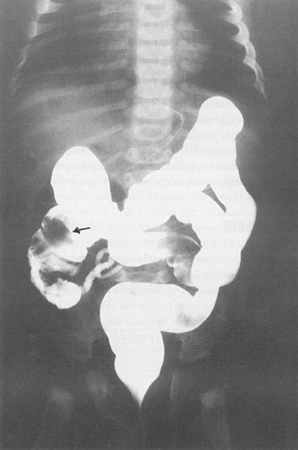

Intussuscepção

geralmente ocorre em lactentes entre 3 meses e 12 meses de idade que apresentam cólica abdominal, flexão das pernas, febre, letargia e vômitos; a púrpura de Henoch-Schönlein (PHS) pode ser um fator causador em crianças mais velhas (geralmente com <11 anos de idade); queixas abdominais vagas; cólica abdominal intensa; as crianças podem ficar inconsoláveis

Exame físico

pode apresentar sangue macroscópico ou oculto que pode estar misturado com muco e ter um aspecto gelatinoso avermelhado, além de desconforto abdominal e massa abdominal à palpação; crianças mais velhas podem apresentar sinais de PHS (rash de púrpura palpável, sangue nas fezes)

Primeira investigação

Outras investigações

- tomografia computadorizada (TC) de abdome e pelve:

lesão em alvo: massa intraluminal de tecido mole, com uma área de gordura excentricamente posicionada; massa reniforme: alta atenuação periférica e atenuação central mais baixa; massa em forma de salsicha: áreas alternadas de baixa e alta atenuação representando a parede intestinal menos espaçada, gordura mesentérica e/ou fluido e gás intestinal